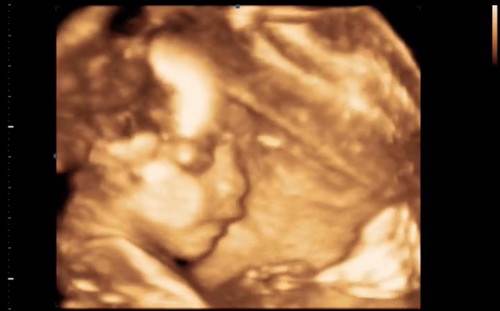

ขอดู 4มิติ. คุณแม่ๆๆหน่อยค่ะ

4มิติ. หลับนิ่งหลับลึก จริงๆๆ???????❤️❤️

28w+5d ลูกสาวจ้า

ซาวตอน32วีคจ้า

20+4 คะได้ลูกสาว

ซาวตอน21weeksครับ

ลูกชายค่า 32 w

28 w ลูกสาวค่า 👧

ลูกชายจ้าาา 35w

ซาวตอน22w6d ค่ะ😍

ตอน 20 วีคจ้าา